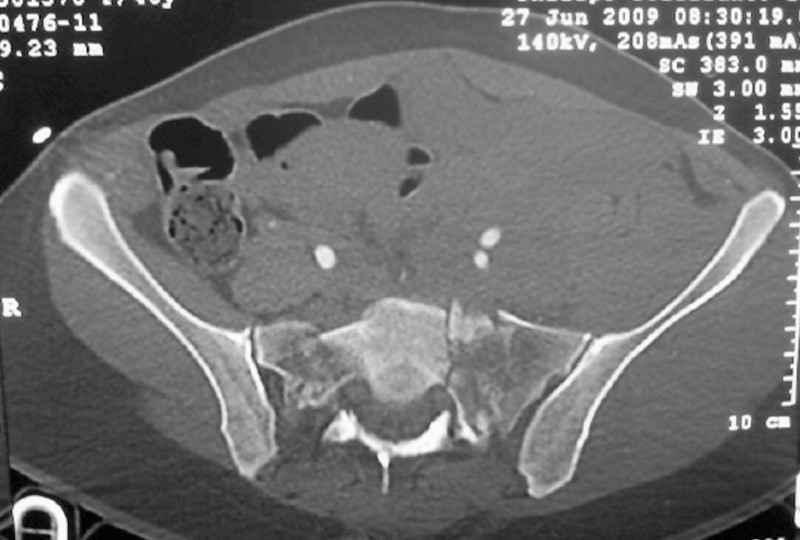

This patient has extensive and complicated skeletal injuries...much more data (such as additional relevant images and clinical information regarding the soft tissues and overall patient status) would help us formulate an informed plan.

The sacral pattern alone is quite difficult and seems to be some version of an H-pattern, but I can’t tell from these films.

General condition is fine except for an intractable pelvic pain, no associated injuries (only ankle fracture), no sciatic nerve injury.

The soft tissues are also in mild condition, buttock hematoma and probably a Morel-Lavalle. I send some more CT images. There are some conminution in the posterior column (I don’t have images now). The patient is scheduled for surgery next Monday. The plan is percutaneous sacral fixation and then ilioinguinal approach .

I am a huge fan of closed reduction and percutaneous posterior pelvic fixation, but that particular sacral injury warrants an open reduction.

I’d begin with that in order to have a high quality osseus foundation for subsequent acetabular repair.